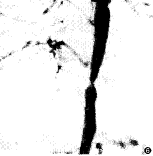

7例中有4例进行了DSA检查,其中3例肾性高血压患者2例见患肾动脉细小,实质期患肾仅见少许染色(图5)。1例多发性大动脉炎患者DSA示降主动脉膈段一明显狭窄,肋间动脉、膈动脉增粗并见迂曲增粗的侧支循环,右肾开口处狭窄,肾动脉下至第3~4腰椎水平间腹主动脉段狭窄,腰动脉增粗(图6、7)。

图1 团注试验剂量后肾动脉水平降主动脉内信号强度-时间曲线 图2、3 肾性高血压患者。平扫时右肾体积明显缩小,DCE-MRA示右肾动脉细小,分为3支,发自主动脉 图4 大动脉炎患者。降主动脉膈段明显狭窄,右膈动脉增粗,肾动脉水平以下节段性不规则狭窄,双肾动脉开口处狭窄 图5 同图2病例。血管造影示右肾动脉细小,分为3支,右肾实质未显影 图6、7 同图4病例。血管造影示降主动脉膈段明显狭窄,右膈动脉及肋间动脉增粗迂曲,肾动脉水平以下节段性狭窄,右肾动脉开口狭窄